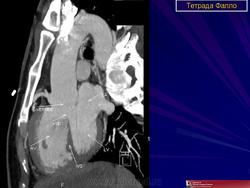

ССС. Тетрада Фалло. +

Тетрада Фалло